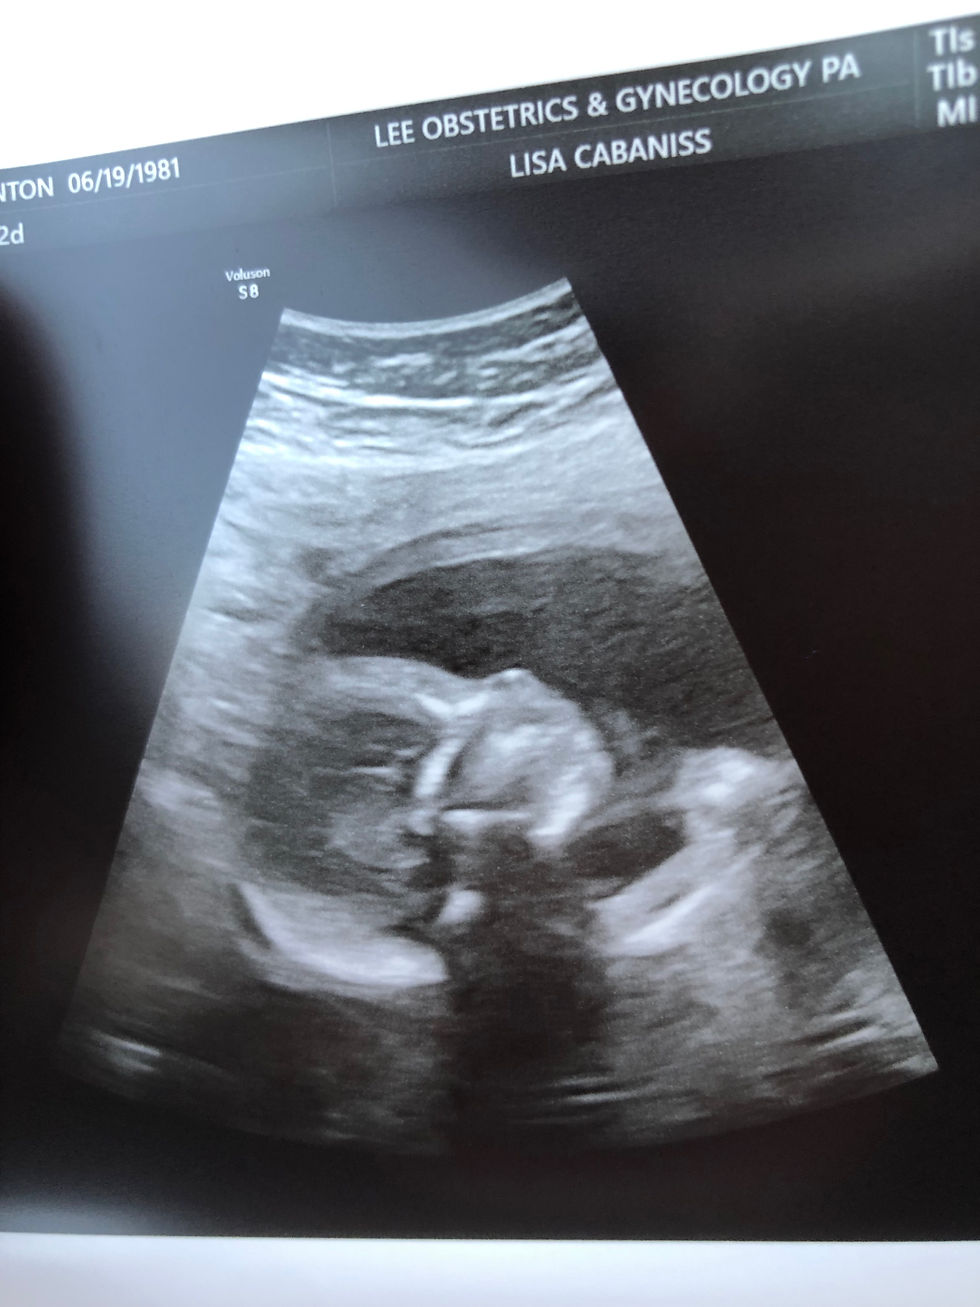

New baby anatomy scan! We're not finding out sex, for the first time.